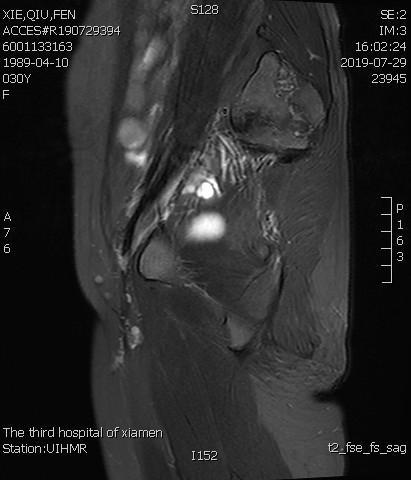

术后复查MRI显示子宫明显缩小,腺肌瘤明显坏死吸收

例3

中年患者,发现“子宫腺肌症”10年余,近5年痛经、月经量增多等症状明显加重,导致贫血,严重影响生活质量。

- 术前彩超、磁共振检查显示子宫明显增大,子宫前壁可见弥漫型子宫腺肌症病灶,合并粘膜下、肌壁间子宫肌瘤。

横断位

冠状位

矢状位